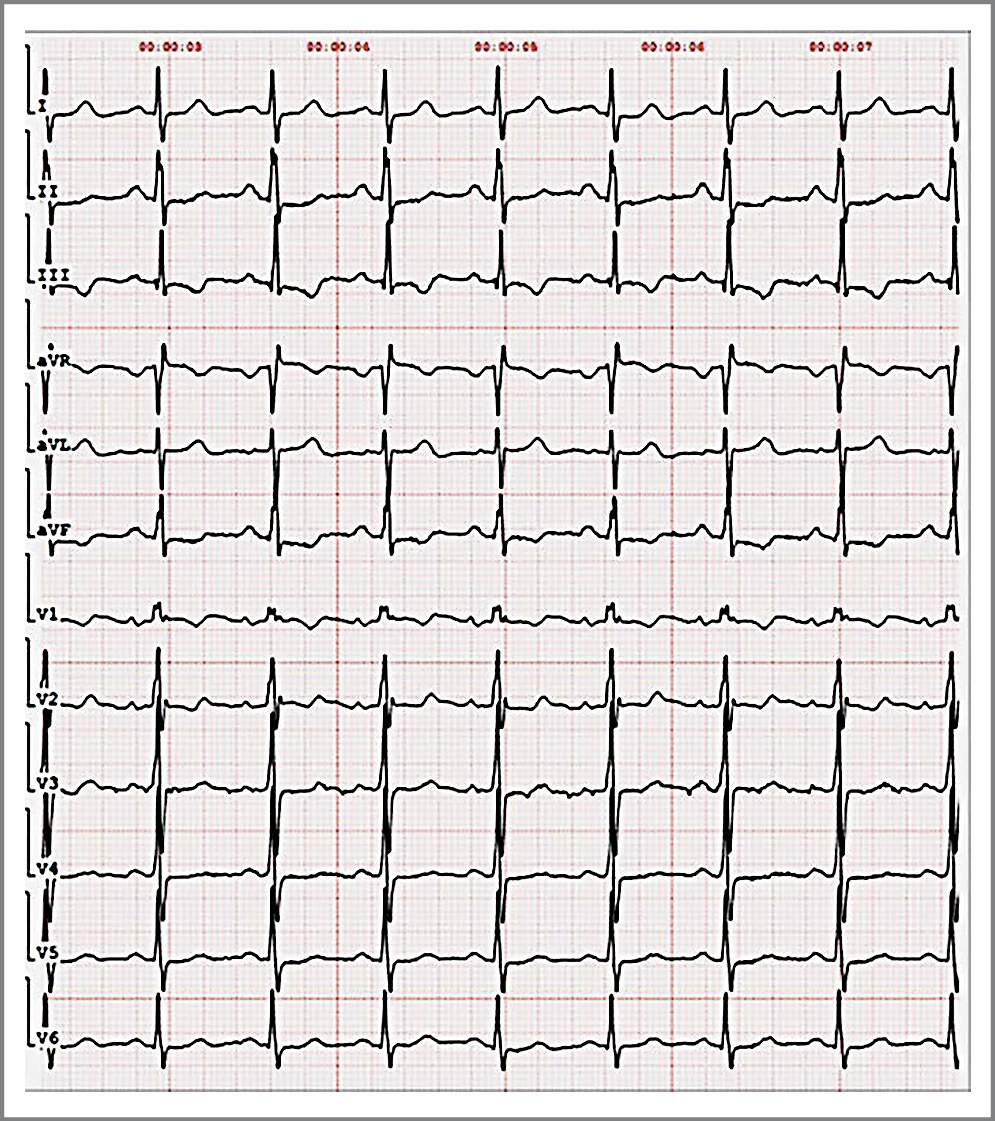

На электрокардиограмме при поступлении зарегистрирован синусовый ритм с частотой сердечных сокращений 89 уд/мин, отклонение электрической оси сердца влево, P-pulmonale, признаки гипертрофии ПЖ (рис. 4).

Рис. 4. Электрокардиография больной при поступлении. / Fig. 4. Electrocardiography of the patient on admission.